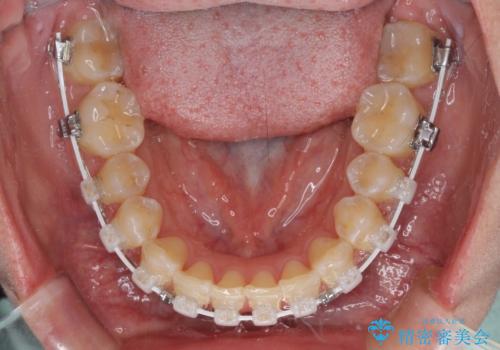

- 矯正装置

- 審美装置

- 上下前歯隙間と正中のズレを改善したいとのことで来院された患者様です。

自己管理を減らしたいとのことで、ワイヤー装置による矯正治療を行うこととしました。

正中がなかなか合わずに、2年近くの治療期間を要しました。